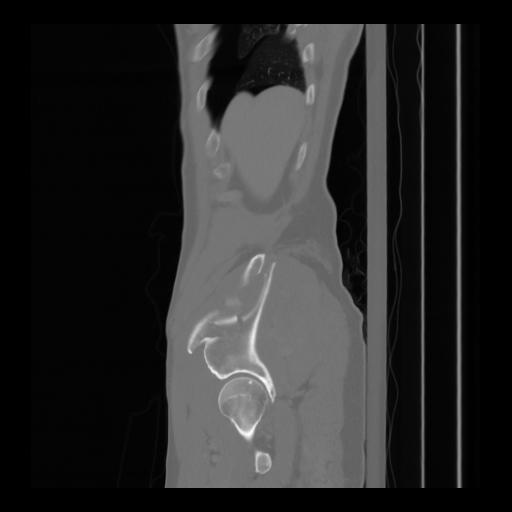

36 CUERPO,CE,Sagittal,3.000,CUERPO,Sagittal,